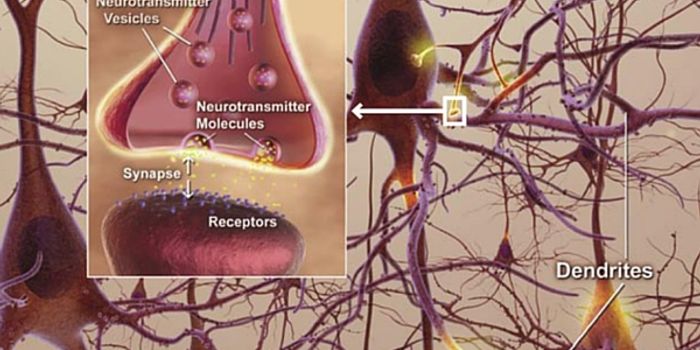

FEB 18, 2022NeuroscienceIon channels are crucial for neural communication; they control the flow and gradient of charged particles, creating ele ...

MAR 01, 2016NeuroscienceThe vast network of neurons, dendrites, axons and other hardware that is responsible for sending messages all over the b ...